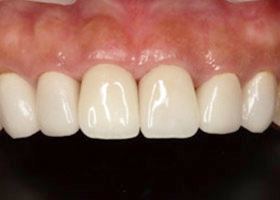

8. 術後口內特寫。